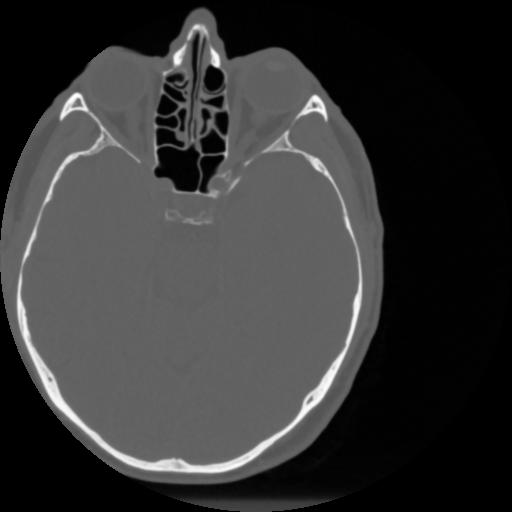

4 CEREBRO,,Vol,0.5,CEREBRO,,